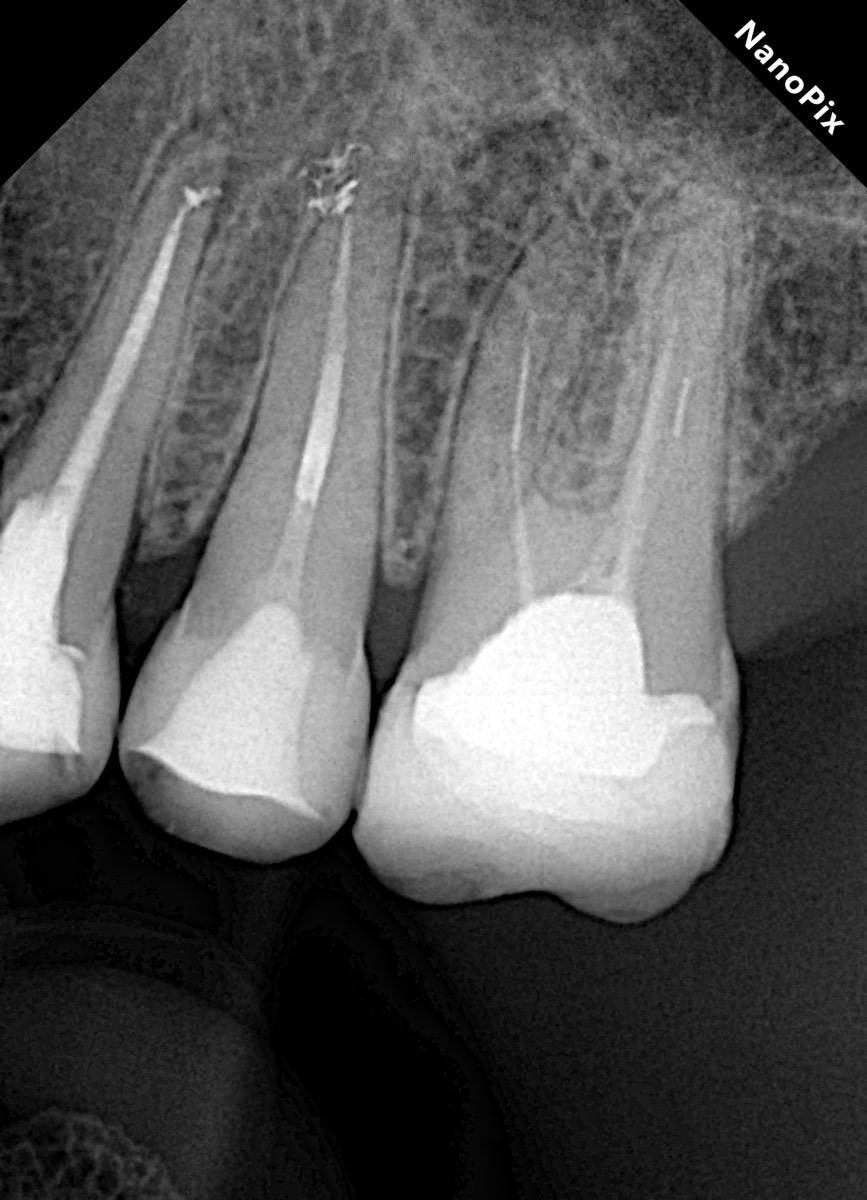

Гарриевич Опубликовано 31 января Автор Поделиться Опубликовано 31 января Когда в твоем кресле оказывается пациент с редким заболеванием «стоматолог-терапевт» работать всегда… легче. Именно! Потому что ты на 100% уверен, что этот человек понимает разницу между «гарантия» и «прогноз», а он на 100% уверен, что ты тот кто ему нужен. Зуб 4.7 со сложной анатомией, ступенькой в мезиальной системе, двойным изгибом, пропущенным каналом и апикальным периодонтитом. Реколл 1 год И сам осмотр через 1 год 4 1 1 Ссылка на комментарий

Гарриевич Опубликовано 18 марта Автор Поделиться Опубликовано 18 марта В 13.03.2026 в 15:26, Doc сказал: Круто! То, что вынимается, доктору вернуть надо или в металлолом сдать? :))) Обычно мы сдаем в чернмет, какие никакие деньги)) Реколл 3 года 1 Ссылка на комментарий

Гарриевич Опубликовано 3 апреля Автор Поделиться Опубликовано 3 апреля Еще один осмотр спустя 3 года и полное заживление 2 1 Ссылка на комментарий